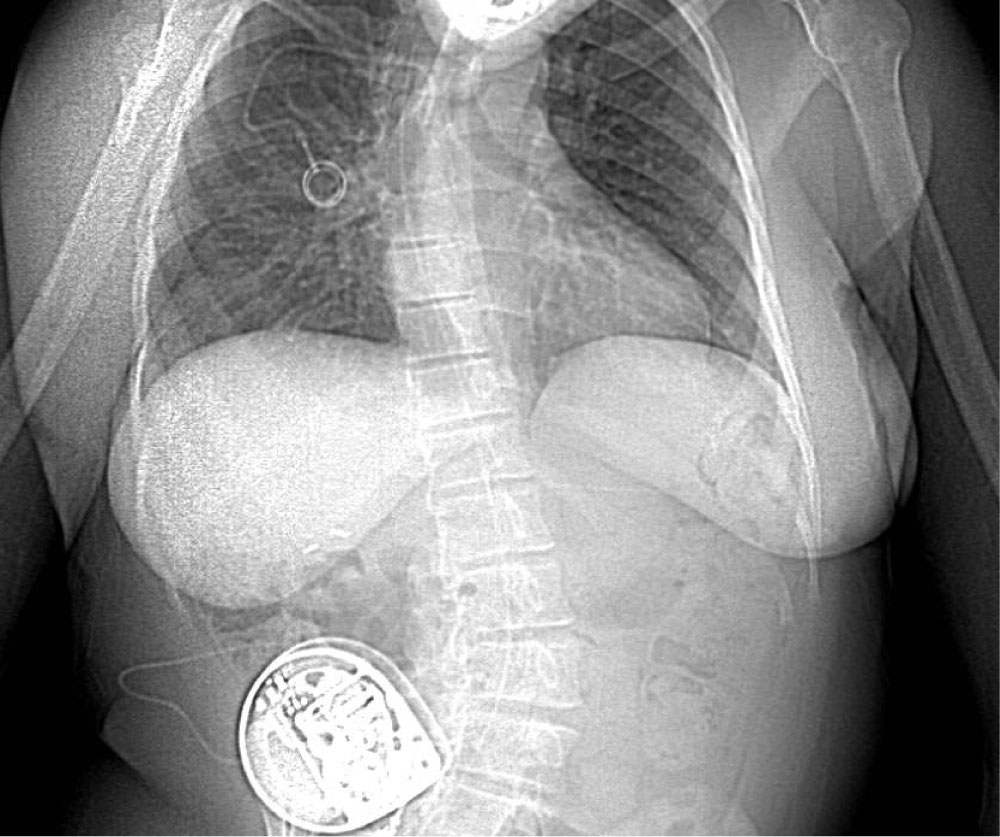

This patient was also benefiting from a continuous intrathecal baclofen pump at a dosage of 360 µg per 24 hours implanted 10 years ago to relieve her spastic tetraparesis secondary to cerebral palsy. The pain specialist who had placed the ITB pump was consulted. A 20-gauge Medtronic intrathecal baclofen infusion catheter had been placed in the median position at the L3-L4 interspace with the tip in the mid-thoracic region. The rest of the catheter had been tunneled in the subcutaneous tissue lateral and inferior to the right costal margin and connected to the Medtronic pump situated in the abdominal subcutaneous tissue (Figure 1). A recent CT-scan was available to confirm these informations, and also showed the subcutaneous part of the tunnelled catheter passing over the median lumbar region from the L1 to L3 levels.

Figure 1: X-ray from a thoracoabdominal CT scan of the patient one month prior to the cesarean. Of note the severe kyphoscoliosis of the patient, the subcutaneous ITB pump in the right abdominal wall, and catheter seen to follow the lumbar column up to the thoracic region. View Figure 1

The female patient, 168 cm and 60 kg was wheelchair bound. A rigorous baseline neurological status was obtained, revealing spasticity and tetraparesis of all four limbs with a normal sensory exam. Examination of her back revealed a severe lumbar-dorsal kyphoscoliosis.